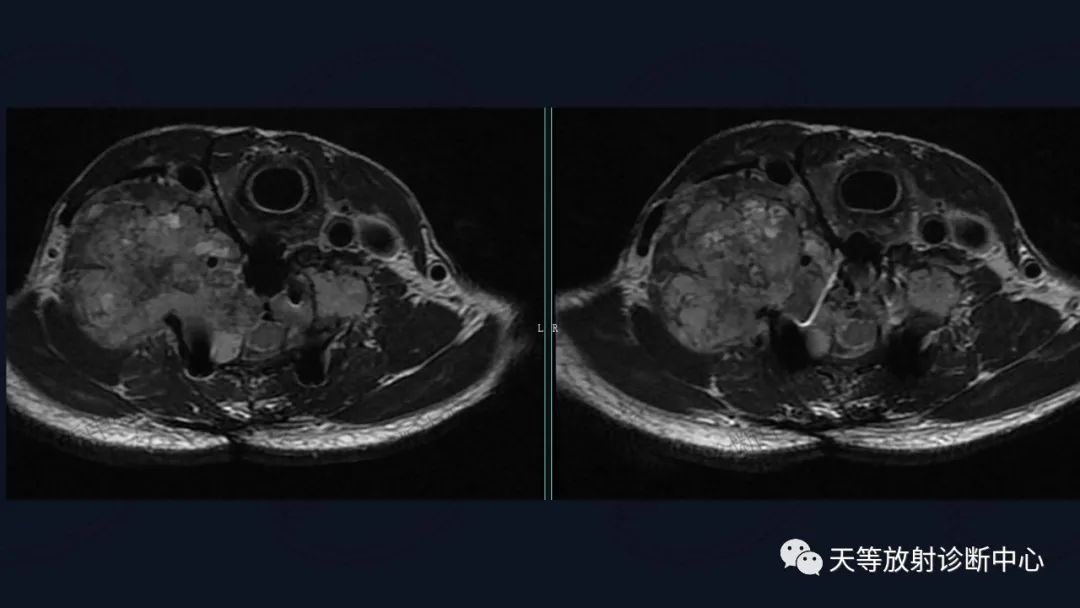

肿瘤复发,椎旁分叶状软组织肿块,内部信号不均,混杂信号,高低信号不等,内见线状小叶间隔。

DWI信号较高,内部钙化灶呈散在泥沙样低信号灶。

3、破坏与软组织不成比例,钙化出现多,钙化呈泥沙样,点状、块状、不规则型 ;

3)MRI信号混杂,钙化呈低信号,软骨粘液、软骨小叶呈高信号影。